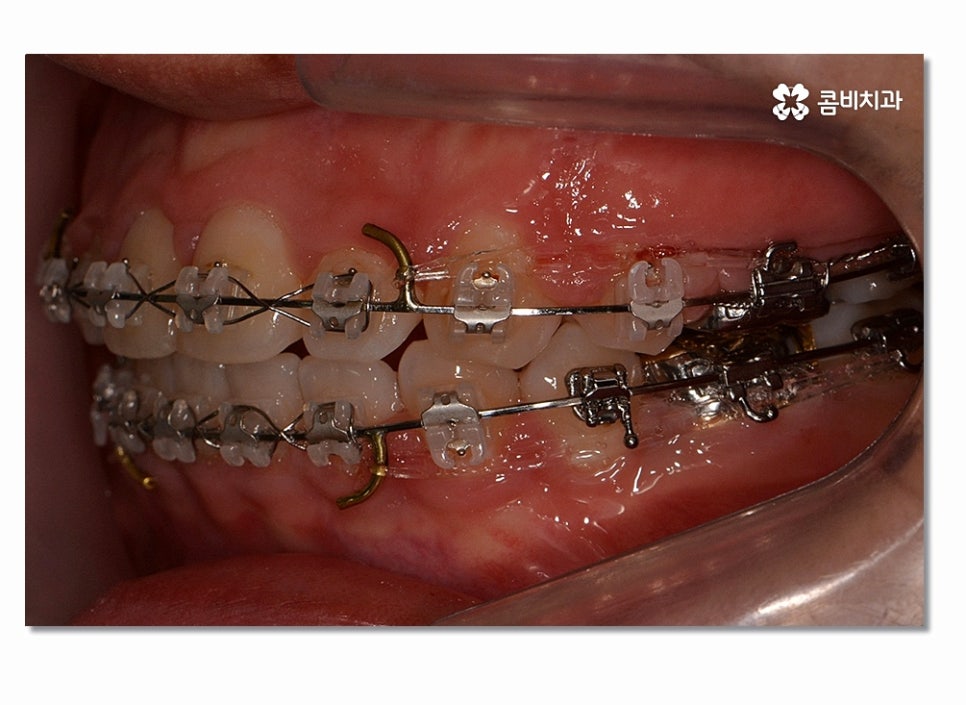

돌출입치아교정이 시작되면 이처럼 전방으로 뻐드러진

앞니를 시간이 지남에 따라서 후방으로 이동시키면서 돌출입이

점점 개선되며 이러한 치열의 변화는 교합도 잘 맞물리도록

신경 써야 하며 얼굴 변화에 대한 부분까지 잘 생각해야 할 수 있어요.

위 사진을 보시면 치아교정 과정을 통해서 치열의 가지런함은 물론이며

측면에서 보더라도 돌출입이 많이 개선된 것을 느낄 수 있을 거예요.